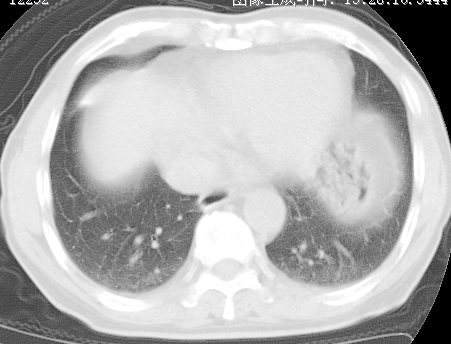

标题: CT24032:男65岁,咳嗽,吸烟20余年,无发热,咳痰 [打印本页]

标题: CT24032:男65岁,咳嗽,吸烟20余年,无发热,咳痰

考虑右肺中叶不张,请大家发表意见

右肺中叶支气管闭塞,中叶肺不张,右侧肺门见肿块影。中心型肺癌的可能大。建议支气管镜检查。

右肺门旁类圆形肿块影,右肺中叶不张,建议纤支镜检查。

1右肺门旁类圆形肿块影,右肺中叶不张,建议纤支镜检查

2右侧胸膜增厚,右侧叶间胸膜区钙化

3右肺下叶小囊状透亮影考虑肺气肿